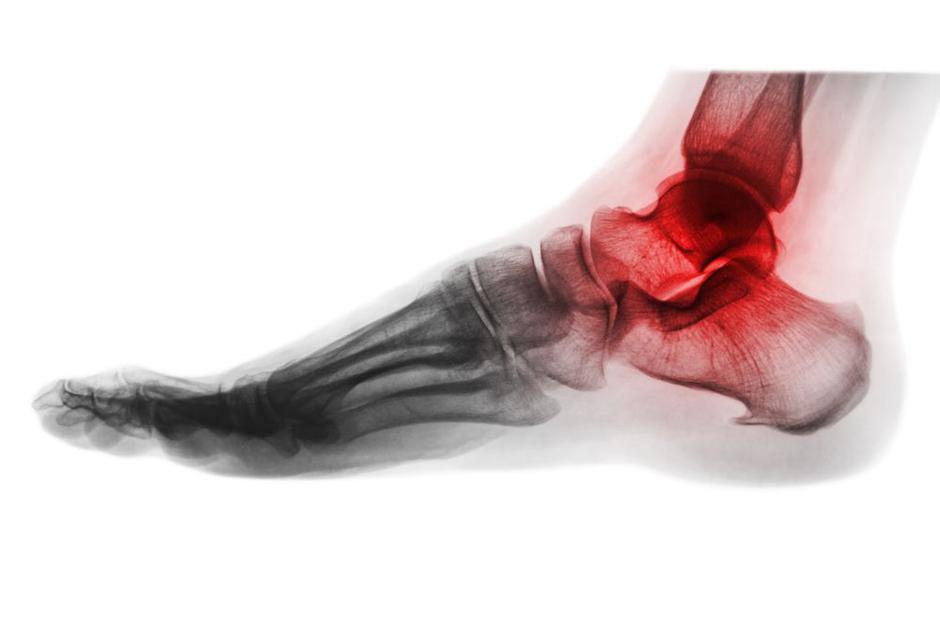

Ste že slišali za Charcotovo artropatijo? Gre za resno, a pogosto spregledano bolezen sklepov, ki se večinoma pojavlja pri bolnikih s sladkorno boleznijo. Poznana tudi kot Charcotov sklep ali diabetična nevropatija, je bolezen razmeroma neboleča, vendar hitro napreduje in prizadene enega ali več sklepov stopal.

Charcotova artropatija (sklep) je resno stanje, ki se običajno pojavi  pri ljudeh s periferno nevropatijo, kot je diabetična nevropatija. Simptomi Charcotove artropatije vključujejo:

• Otekanje sklepa: Prizadeti sklep postane otečen in vnet.

• Bolečina ali neobčutljivost: Lahko se pojavijo bolečine, vendar zaradi nevropatije pogosto ni senzibiletene občutljivosti ali je le-ta zmanjšana.

• Nestabilnost sklepa: Zaradi poškodbe kosti in sklepov postane sklep strukturno spremenjen in nestabilen.

• Deformacije: Z napredovanjem bolezni lahko pride do hudih deformacij sklepov v stopalu, kar vodi do sprememb v hoji in drži.